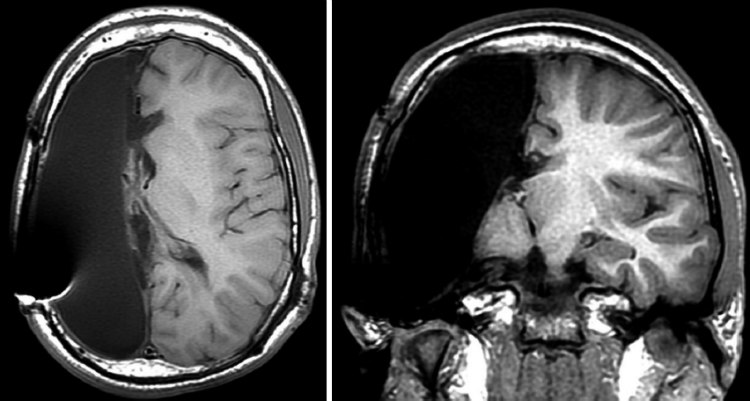

8. When you orgasm, your brain releases so much dopamine that a brain scan would resemble that of someone on heroin.

MRI Dopamine Concentrations

Image Source: Christine Daniloff/MIT

Dopamine is one of the chemicals that affect your mood, the feeling of satiation, desire for intimacy, and also your susceptibility to addictions. Dopamine is the primary neurotransmitter of activities like eating, sex, or recreational drug use result in its release and hence you feel pleasure. When you are sexually aroused its levels rise making you feel good..(1,2)